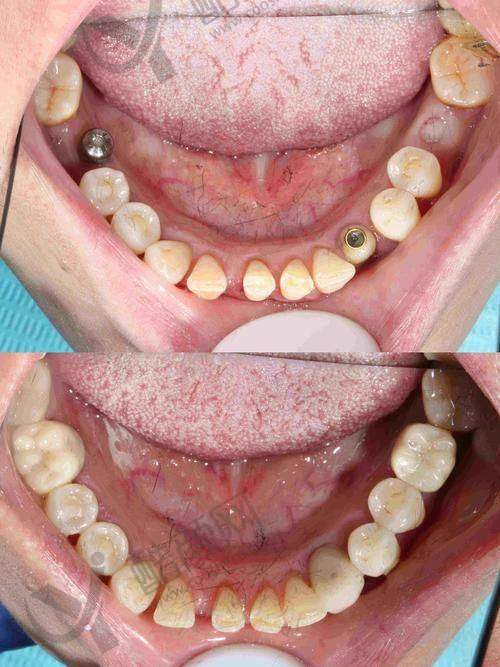

盐城中喜口腔种植医生史衡涛种植牙实例

实例一:患者李先生,因意外导致多颗牙齿缺失,重度影响了咀嚼功能和面部美观。史衡涛医生为他制定了多颗种植的方案,采用微创种植技术,手术过程非常顺利。术后李先生修复良好,种上的牙齿与真牙无异,咀嚼功能也得到了良好的修复,他对治疗成效非常满意。